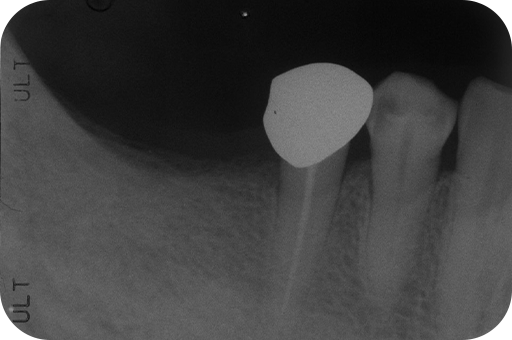

右下5番 感染根管治療

- 右下5番

- 感染根管治療